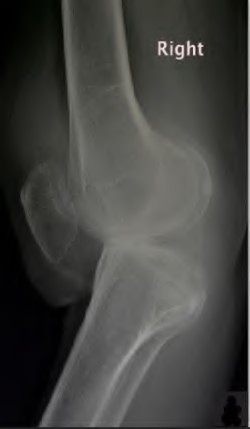

A 55-year-old male presents with isolated medial compartment osteoarthritis of the right knee. He is being evaluated for a medial unicompartmental knee arthroplasty (UKA). Which of the following physical examination or radiographic findings is an absolute contraindication to a medial UKA?

Which of the following is traditionally considered an absolute contraindication to a medial mobile-bearing unicompartmental knee arthroplasty (UKA)?